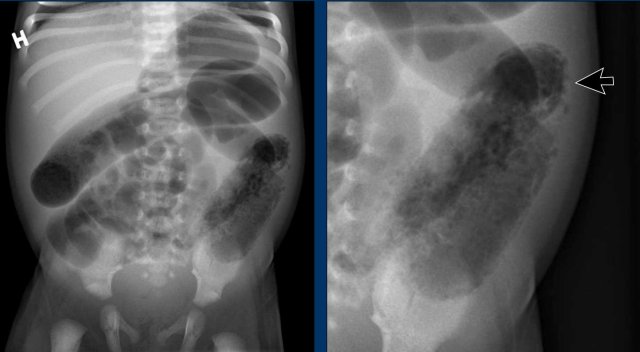

Images

Abdominal radiographs demonstrating dilated bowel loops and asymmetric distribution of air with paucity in the right lower quadrant.